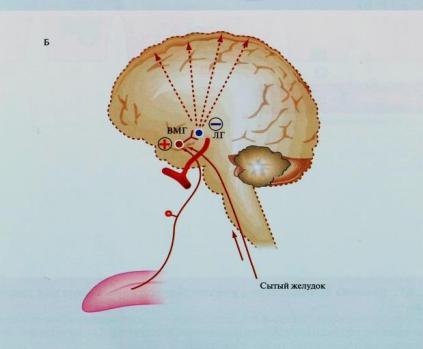

Как работает центр насыщения в гипоталамусе: визуальные иллюстрации